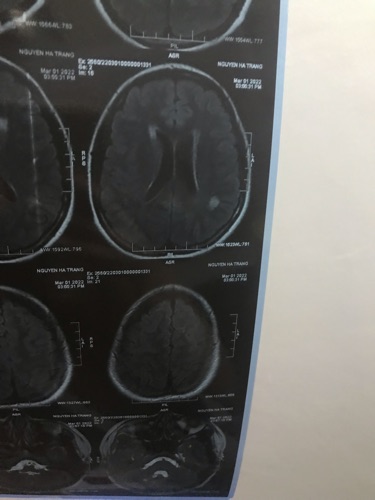

Em chào các bác sĩ ạ. Nay em có đi khám về hậu covid do thường xuyên mất ngủ , khó thở thì được bác sĩ khám nội phát hiện ra hình ảnh chụp MRI có tổn thương nghi ngờ viêm não nhưng do không phải chuyên môn nên bác sĩ khuyên em nên khám chuyên khoa thần kinh, khả năng cao chỗ viêm có từ trước khi em bị covid Em cần nhờ bác sĩ bên mình khoa thần kinh xem giúp em với ạ và nếu khám thì khám viện nào tại HN được ạ. Em cảm ơn ai